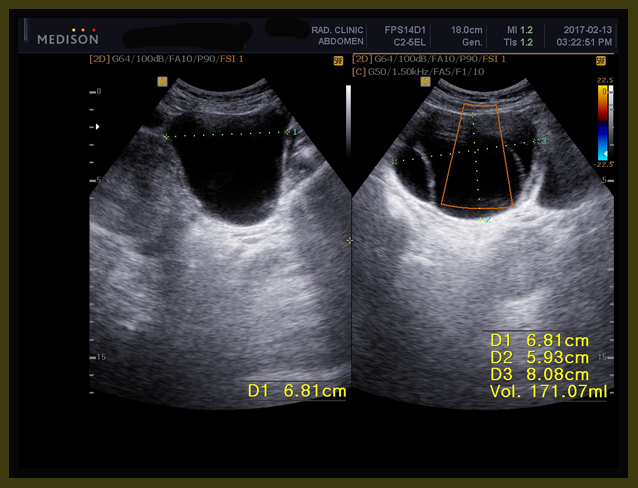

환자는 1년 전에 난소의 양성종양으로 수술을 받았던 경험이 있고, 이번에도 유방수술 이후에 초음파를 보니 83mm x 61 mm x 58 mm의 약 8cm x6cm 정도의 격벽으로 분리된 cystic mass 즉 액상의 종양이 보였고, 또한 13mm, 15 mm의  mass도 발견되었다(2017년 1월 26일 검사).

내원 후에 본원 의뢰하여서 초음파 검사를 하였는데 초음파상의 결과는 이전 병원과 약간의 차이가 있지만 역시 8cm가 넘는 종양이 발견되었다.

골반초음파

1. 6.8cm x 5.9cm x 8.1 cm 크기의 여러 개로 갈라진 격벽을 가지고 있는 액상의 부위가 왼쪽 자궁주위 조직에 보이는데 양성의 혹으로 보인다.

2. 자궁내막의 비후가 관찰된다.

3. 약 3cm 크기의 근종으로 의심되는 부분이 자궁의 아래쪽에 보인다.

1. 6.8cm x 5.9cm x 8.1 cm 크기의 여러 개로 갈라진 격벽을 가지고 있는 액상의 부위가 왼쪽 자궁주위 조직에 보이는데 양성의 혹으로 보인다 (volume 171 CC).

2주간의 한양방 결합요법의 결과 3항에서 보듯이 약 7mm 정도의 전에 잔류 종양으로 보이던 부분이 약간 줄어들었고, 자궁주위에 있던 난소의 종양은 6.8×5.9x 8.1cm의 크기가 5.5×4.7×6.7cm 로 체적대비해서 171 cc가 91 cc로 100%의 종양이 53%로 절반 가량이 줄어들었고, 자궁내벽의 비후는 여전히 보이고, 3cm 크기의 근종으로 보이는 종양은 차이가 없었다.

이후 환자는 2017년 4월 13일 치료 시작한지 2달 만에 다시 에스트로겐 수치와 초음파 검사를 하게 되었다.

1-9

4월 13일 초음파 결과에 의하면 이전에 보이던 우측의 수술부위와 우측 액와림프절 수술부위의 섬유화가 많이 줄었고(2), 선 같은 액상의 7mm 크기의 근육 내의 nodule도 섬유화처럼 변모되었고(3), 골반에 있던 이전이 91cc의 다격벽의 난소종양도  25CC로 줄어들었다. 또한 자궁하부에 보이던 근종으로 의심되는 부분도 3cm에서 2cm로 줄어들었다. 또한 에스트로겐 검사도 이전에 1000이 넘던 수치가 40대로 떨어져서 확연한 에스트로겐의 감소를 알 수 있다.

1. A multiseptated cystic lesion in the left parametrium, cystic ovarian tumor, muchmore regressed(5.5×4.7×6.7cm/91ml ->2.8×3.9×4.5/25ml)

171 ml                                               91 ml                                           25ml